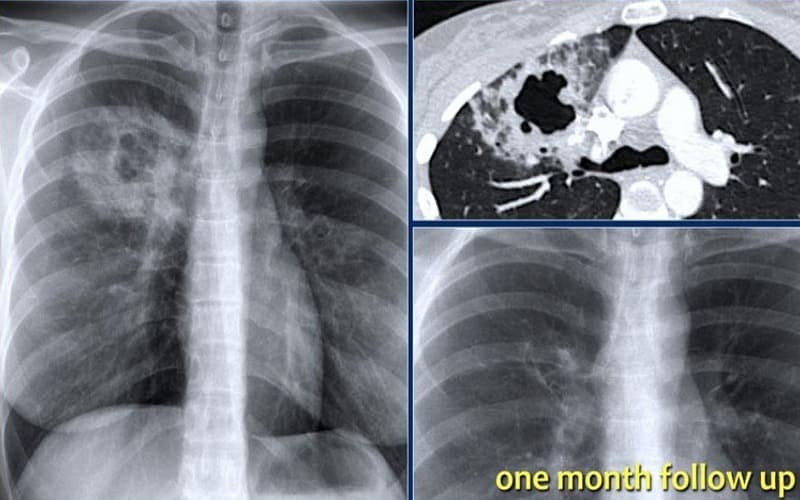

Nhiễm trùng phổi là bệnh gì? Nhiễm trùng phổi, hay còn gọi là viêm phổi, là tình trạng viêm và nhiễm trùng ở phổi hoặc đường hô hấp dưới do vi khuẩn, virus, nấm hoặc các vi sinh vật khác gây ra. Bệnh làm phế nang chứa dịch hoặc mủ, gây khó thở và các triệu chứng liên quan. Viêm phổi do vi khuẩn thường nghiêm trọng hơn và dễ phải nhập viện, trong khi viêm phổi do virus thường nhẹ và tự khỏi.

Như đã nói nhiễm trùng phổi là một bệnh lý nguy hiểm và cũng là nguyên nhân gây tử vong cho nhóm tuổi Trên 65 tuổi và/hoặc dưới 2 tuổi. Hơn nữa nhiễm trùng phổi còn có thể dẫn đến các biến chứng nghiêm trọng như:

- Suy hô hấp hoặc hội chứng suy hô hấp cấp tính (ARDS) .

- Dịch tích tụ quanh phổi (tràn dịch màng phổi).

- Sốc nhiễm khuẩn và Nhiễm trùng huyết. Vi khuẩn gây viêm phổi có thể xâm nhập vào máu, lây lan nhiễm trùng sang các cơ quan khác và dẫn đến nhiễm trùng toàn thân hoặc suy tạng.

- Áp xe phổi